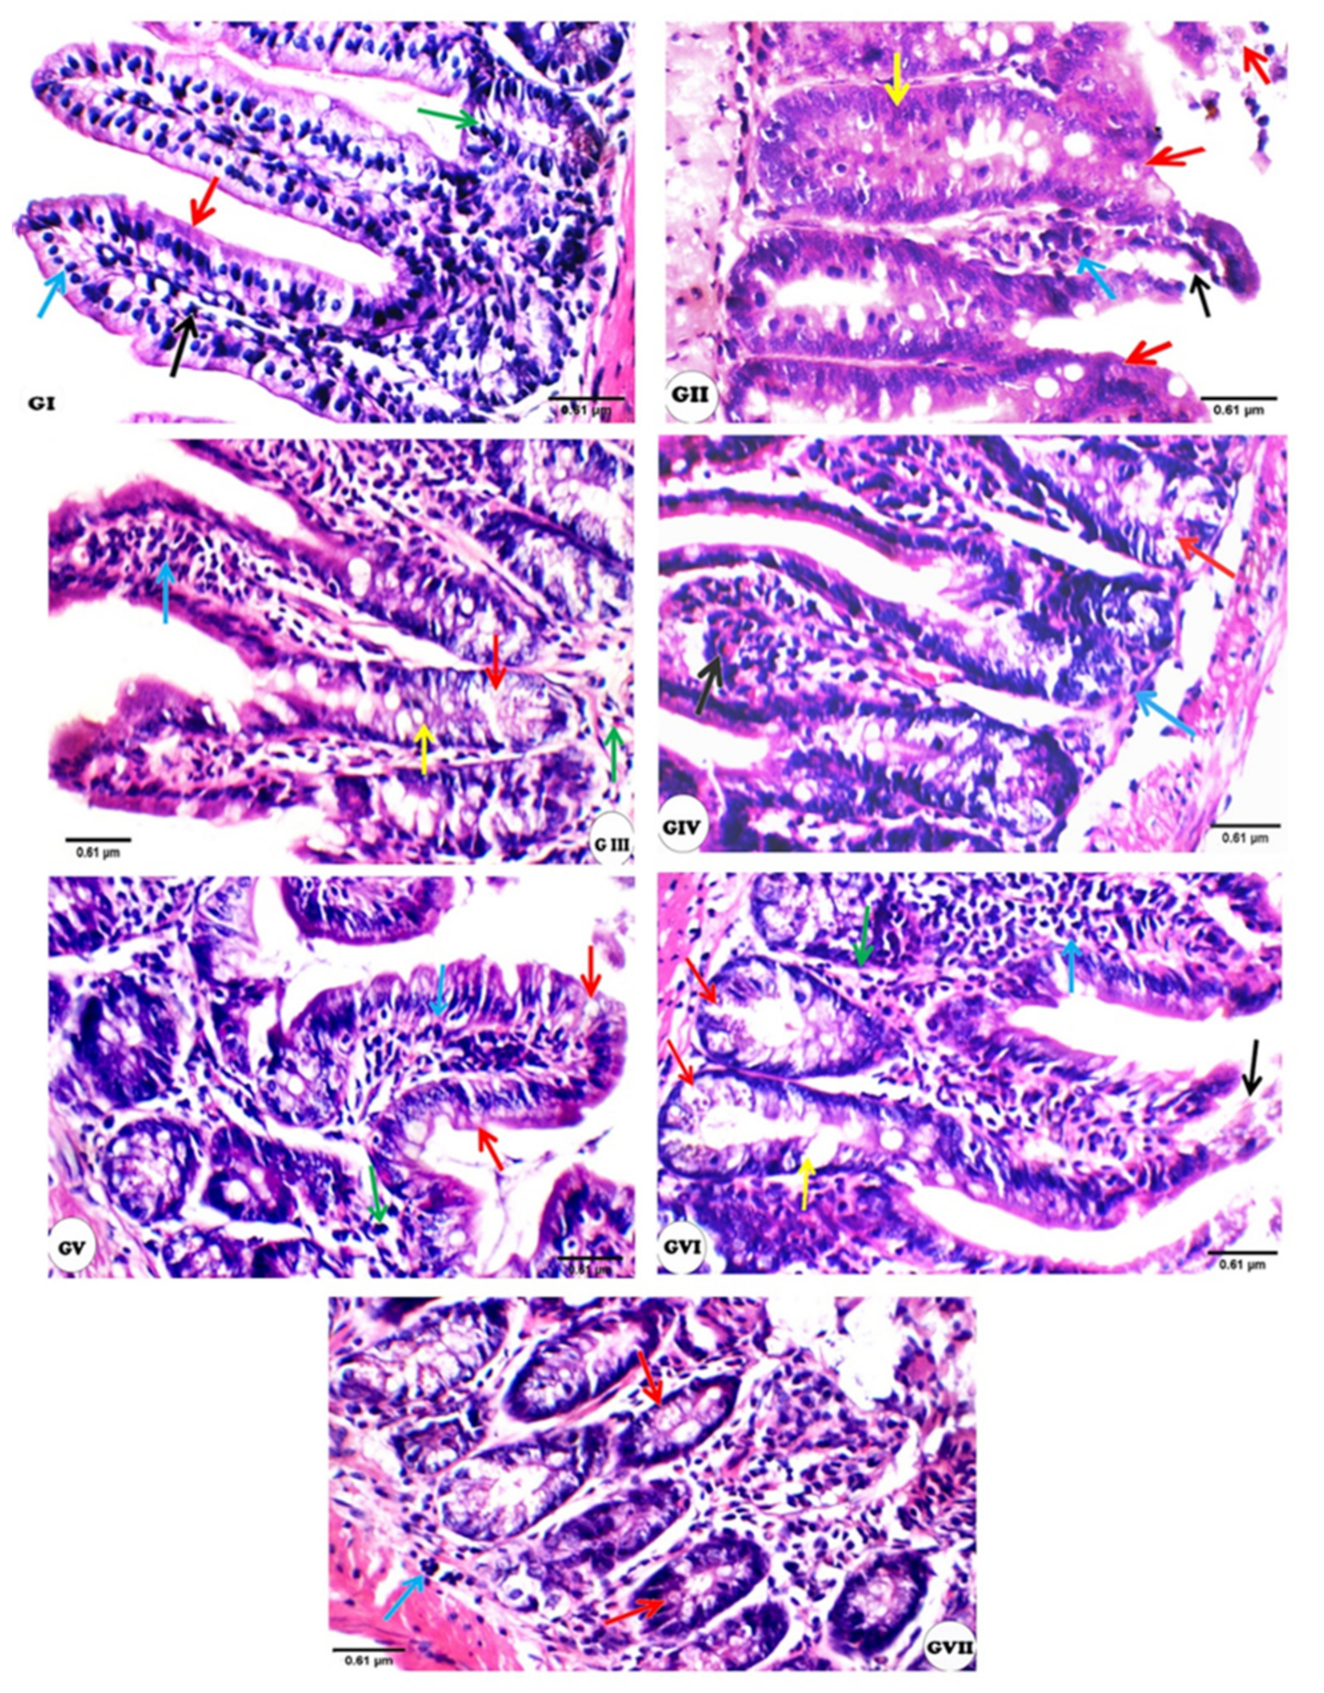

3.3. Histopathological Changes

| Experimental Groups | Mucosal Thickness | Villi | Crypts | Inflammatory Infiltrate | Oocysts | Submucosa | Musculosa |

|---|---|---|---|---|---|---|---|

| I | 0 | 0 | 0 | 0 | 0 | 0 | 0 |

| II | ++ | ++ | ++ | ++ | ++ | ++ | 0 |

| III | 0 | + | + | + | + | + | 0 |

| IV | 0 | + | + | + | + | 0 | 0 |

| V | + | ++ | + | ++ | + | ++ | 0 |

| VI | 0 | + | + | ++ | ++ | 0 | 0 |

| VII | + | ++ | + | ++ | + | + | 0 |